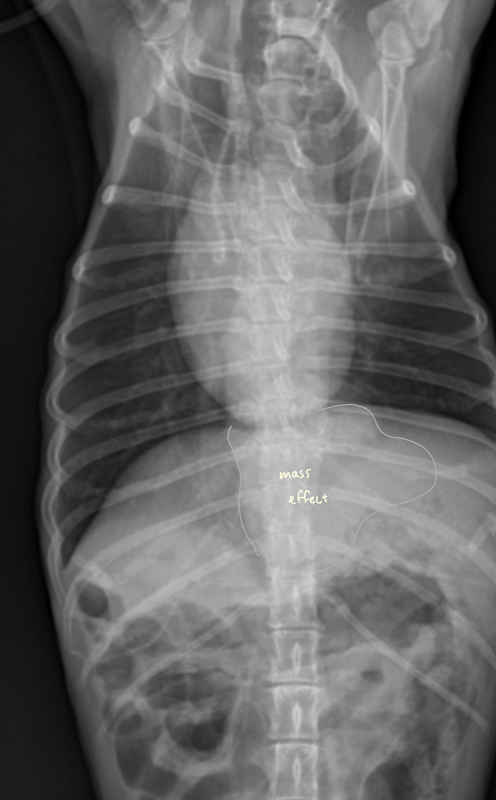

โ ๊ณจ๋ฐ๊ฐ ๋ด์์ ์๋ mass

- 4๊ฐ์์งธ ์ฌํ ๋ณ๋น + ์์๋ถ์ง, ์ฒด์ค ๊ฐ์, ๊ฐํ์ ๊ตฌํ ๋ก ๋ด์.

- Mass๊ฐ ๊ณจ๋ฐ๊ฐ ์์์ ์๋ผ๋ฉด ๊ฒฐ์ฅ๊ณผ ์๋๋ฅผ ๋ฐ์ด๋ด๊ณ , ์ ์ฑ ๋ณ๋น๋ฅผ ์ ๋ฐํจ.

- Leiomyoma๋ก ์ง๋จ๋จ.

โ ๋ด๊ฐ ์์ชฝ์์ ์๋ mass

- ๊ณจ๋ฐ๊ฐ๊ณผ ๋ฌ๋ฆฌ ๋ณต๊ฐ์๋ ์ฌ์ ๊ณต๊ฐ์ด ์์ด, ๋ด๊ฐ ๋ฐ๊นฅ์์ ์๊ธด mass๋ผ๋ฉด ๊ธธ์ ๋ง์ง ์์.

- ๊ทธ๋ฌ๋ ๋ด๊ฐ ์์ ์๊ธด mass๋ผ๋ฉด ๋ถ๋ณ์ด ๊ณ์ ์ถ์ ๋จ.

- ์กฐ์์ ๋ ์ผ์ ํ ๋๋น๋ก ํต๊ณผํ์ง ๋ชปํ๊ณ ๋งํ.